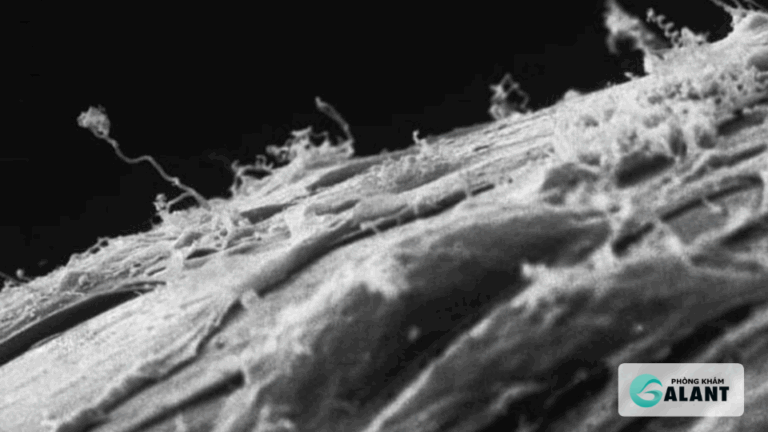

Trong những năm gần đây, tỷ lệ mắc bệnh giang mai đang gia tăng trở lại trên toàn cầu, trong đó có Bệnh Giang Mai ở MSM (Men who have Sex with Men) và cộng đồng LGBT. Điều này không…